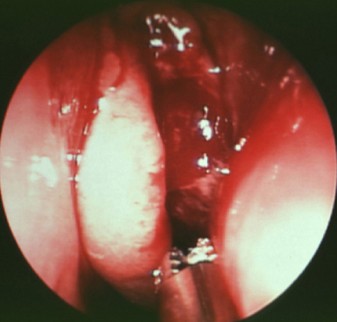

张胜利 耳鼻喉主任

擅长:擅长于各类耳鸣耳聋、中耳炎、鼓膜穿孔、鼻窦炎、鼻息肉、扁桃体炎、腺样... 【详情】

刘大顺 博士/主任医师

擅长:擅长各种鼻炎手术、鼾症手术及头颈部肿瘤手术治疗。尤其擅长慢性鼻窦炎的... 【详情】